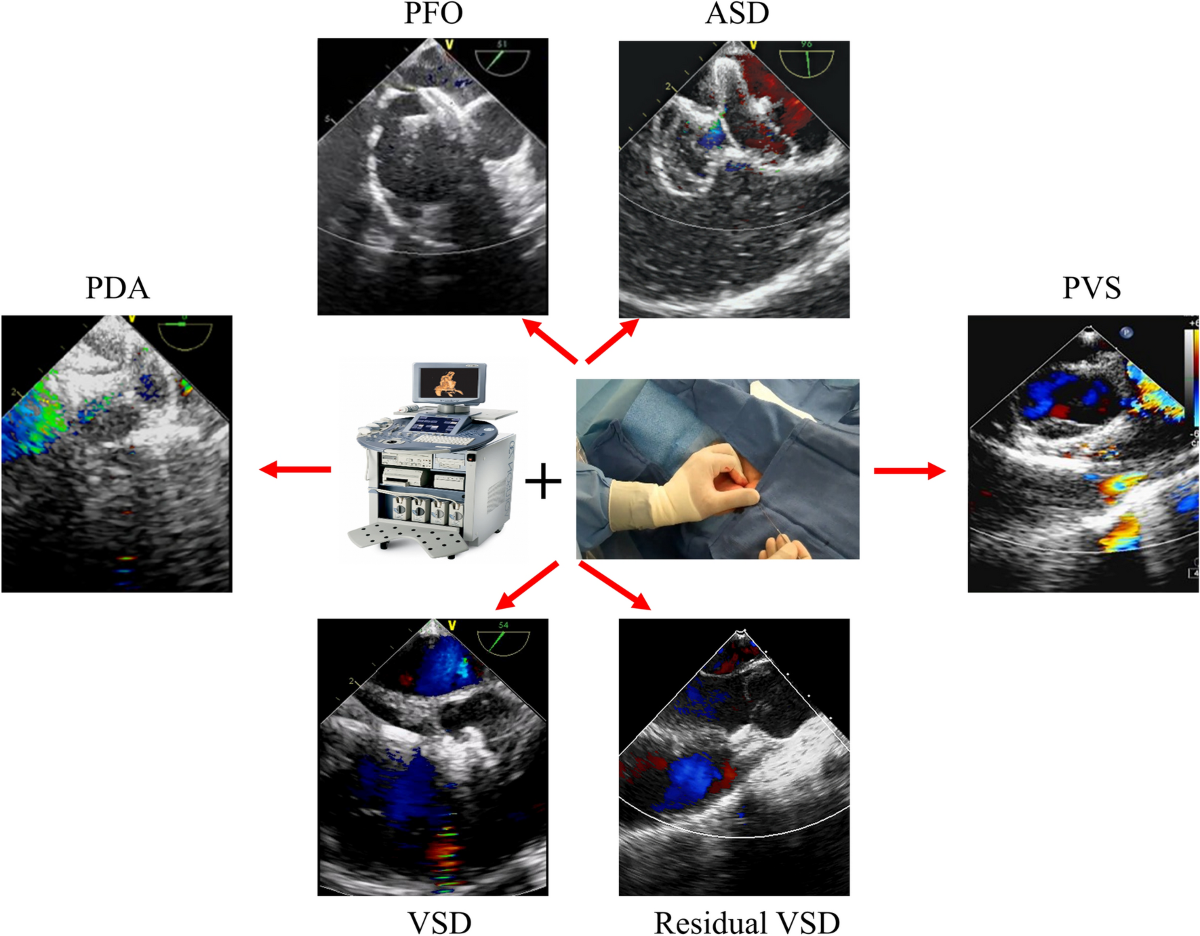

pda pfo heart sale